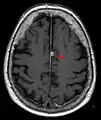

T1 (note CSF is dark) with contrast (arrow pointing to meningioma of the falx)

- T1-weighted (T1W) images: Cerebrospinal fluid is dark. T1-weighted images are useful for visualizing normal anatomy.